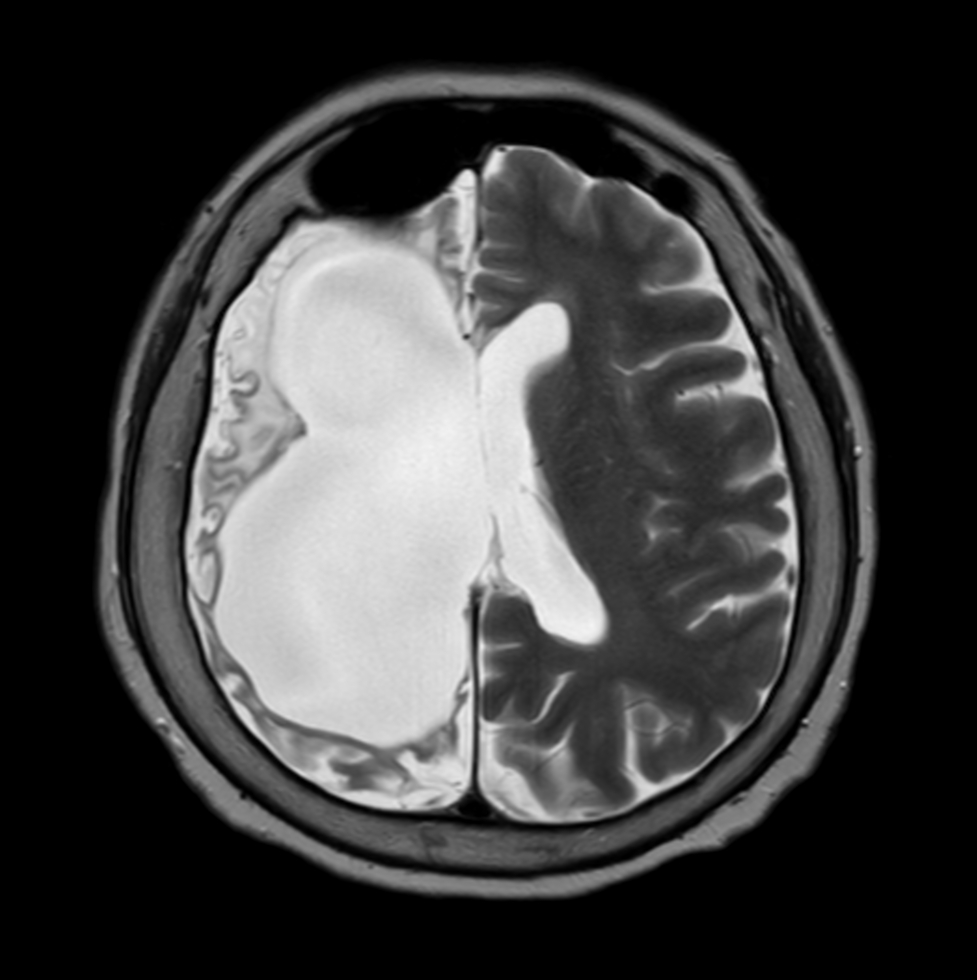

Axial T2w TSE